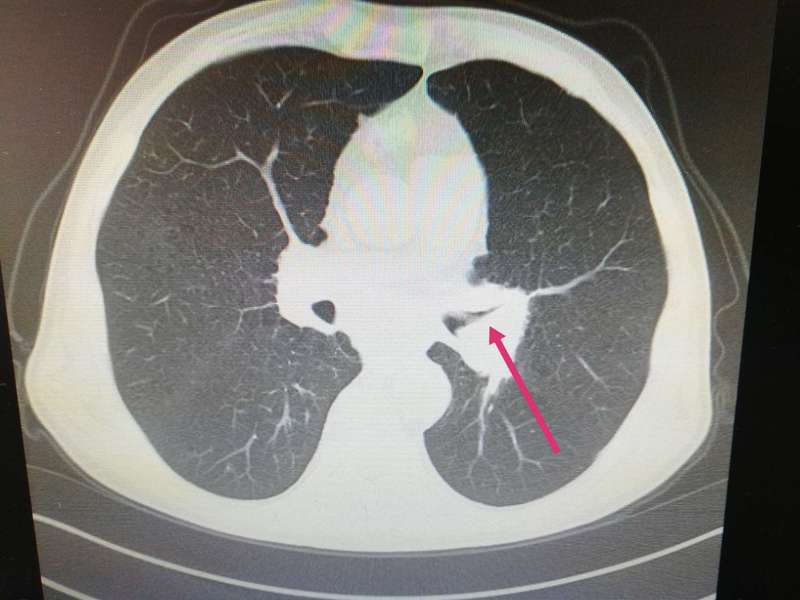

老年男性,刺激性咳嗽癥狀嚴(yán)重,可待因都止不住咳嗽。入院查體發(fā)現(xiàn)左側(cè)中心型肺癌,左上葉支氣管狹窄閉塞。 病理結(jié)果為腺癌。如圖1.2所示,為治療前病人的胸部CT圖片。 介入治療兩次后,病人咳嗽癥狀緩解,停服可待因,咳嗽亦無(wú)反復(fù)。 復(fù)查CT,患者原來狹窄閉塞的支氣管已經(jīng)復(fù)通。 腫瘤明顯縮小,縮小到幾乎看不到了才是這個(gè)病人好轉(zhuǎn)的原因。 介入治療后肺門腫塊消失,氣管復(fù)通。 介入治療兩次后,病人咳嗽癥狀緩解,停服可待因,咳嗽亦無(wú)反復(fù)。 復(fù)查CT,患者原來狹窄閉塞的支氣管已經(jīng)復(fù)通。 腫瘤明顯縮小,縮小到幾乎看不到了才是這個(gè)病人好轉(zhuǎn)的原因。 晚期肺癌,做介入治療。